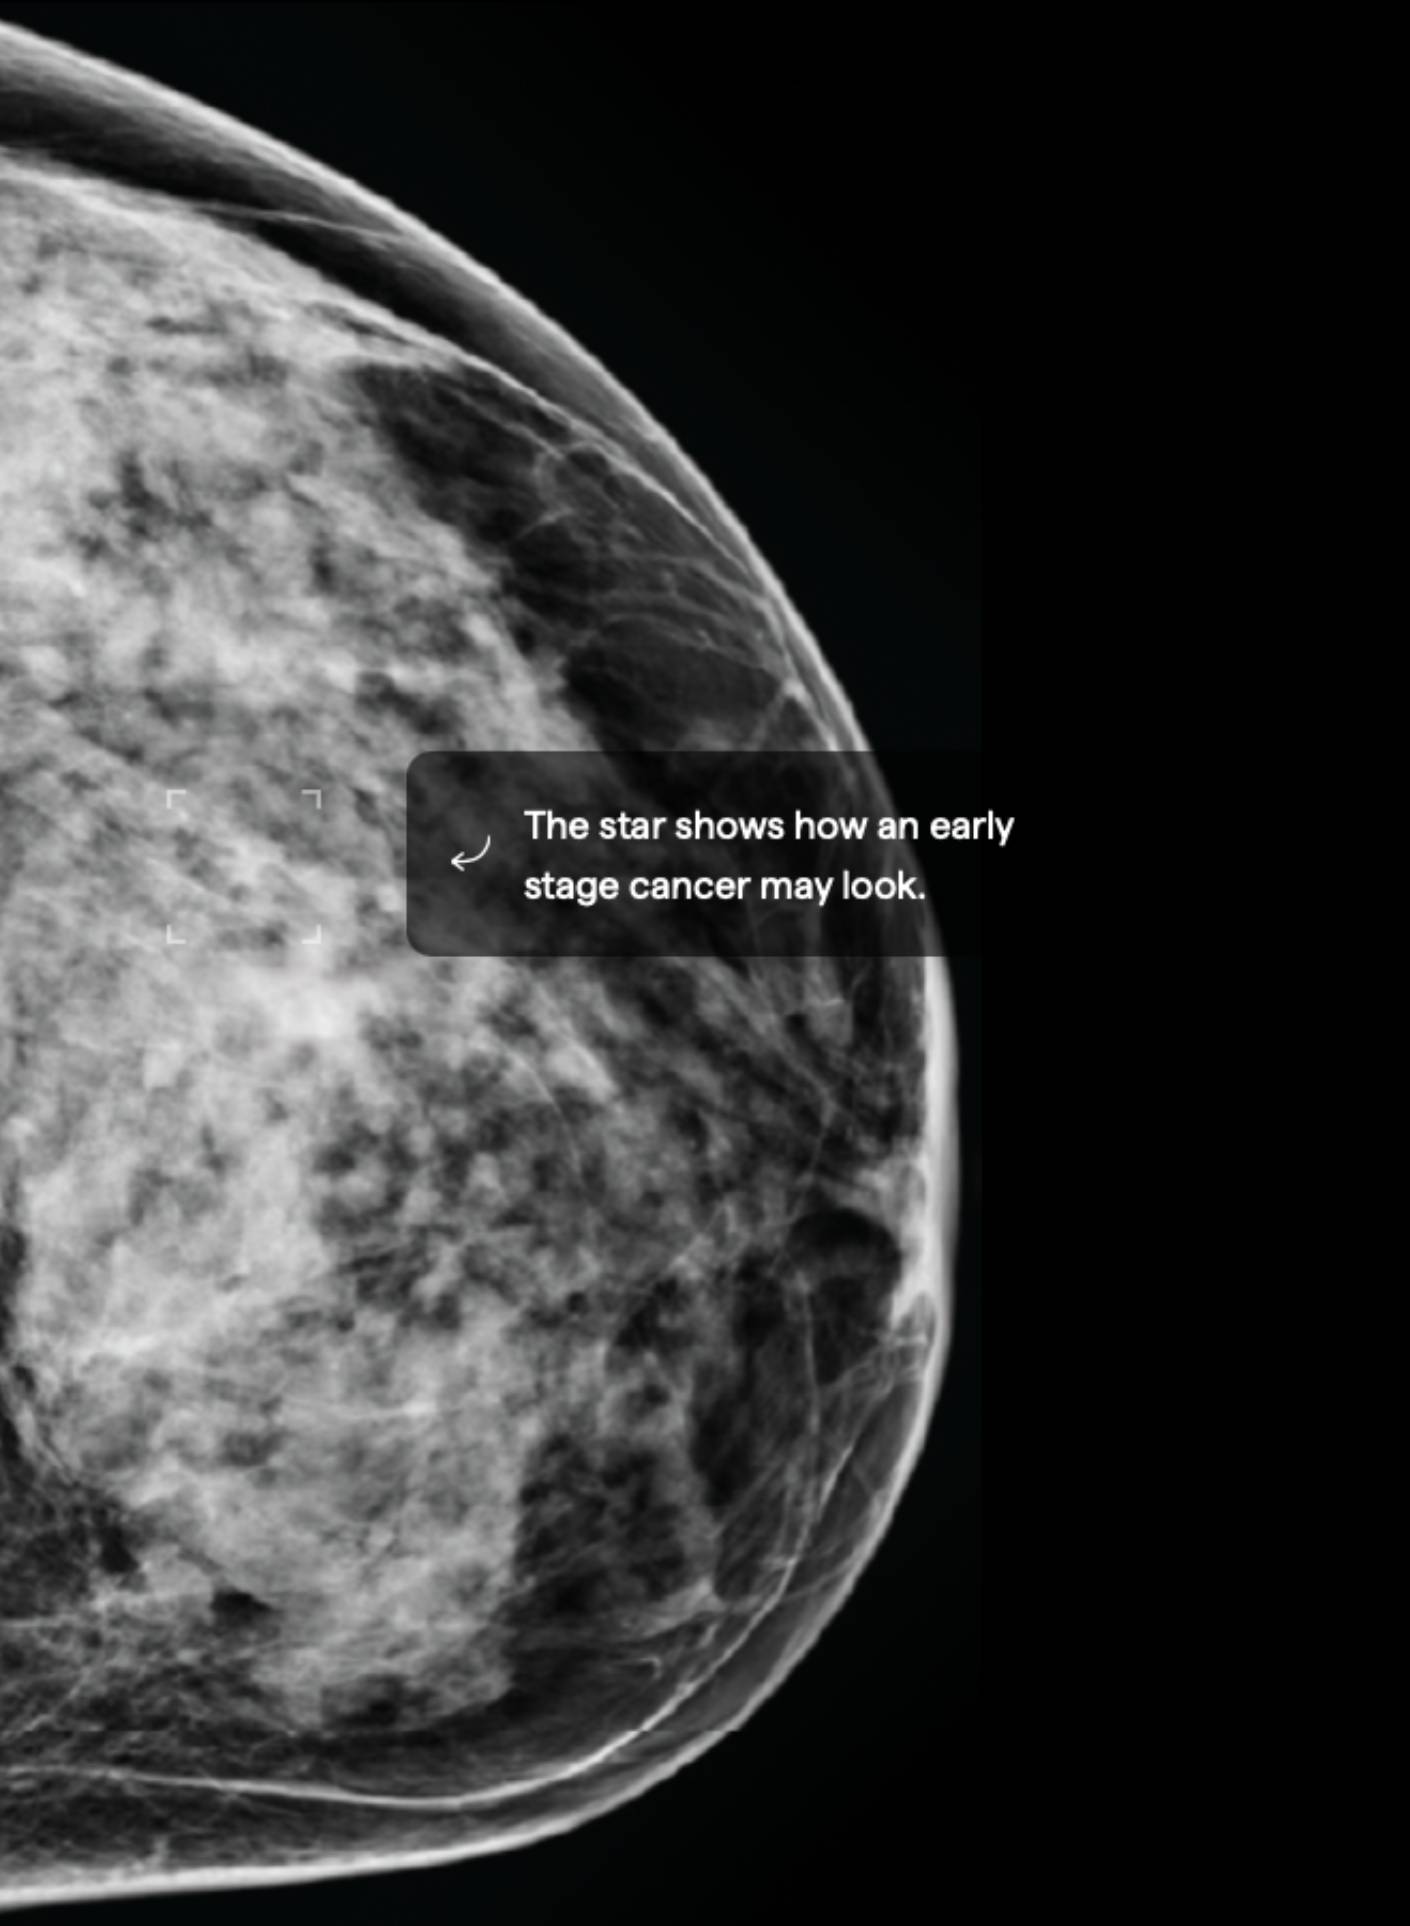

15.5% Mammographic Density

About 10% of female breasts fit category “D”. They are referred to as “extremely dense breasts”.1

Women with high breast density may have a greater risk of developing breast cancer. High breast density also makes it harder to detect breast cancer.3 Consider asking your doctor about adding ultrasound and/or MRI imaging to your screening schedule. Also consider asking about a risk assessment to help both of you better understand your lifetime risk for breast cancer.